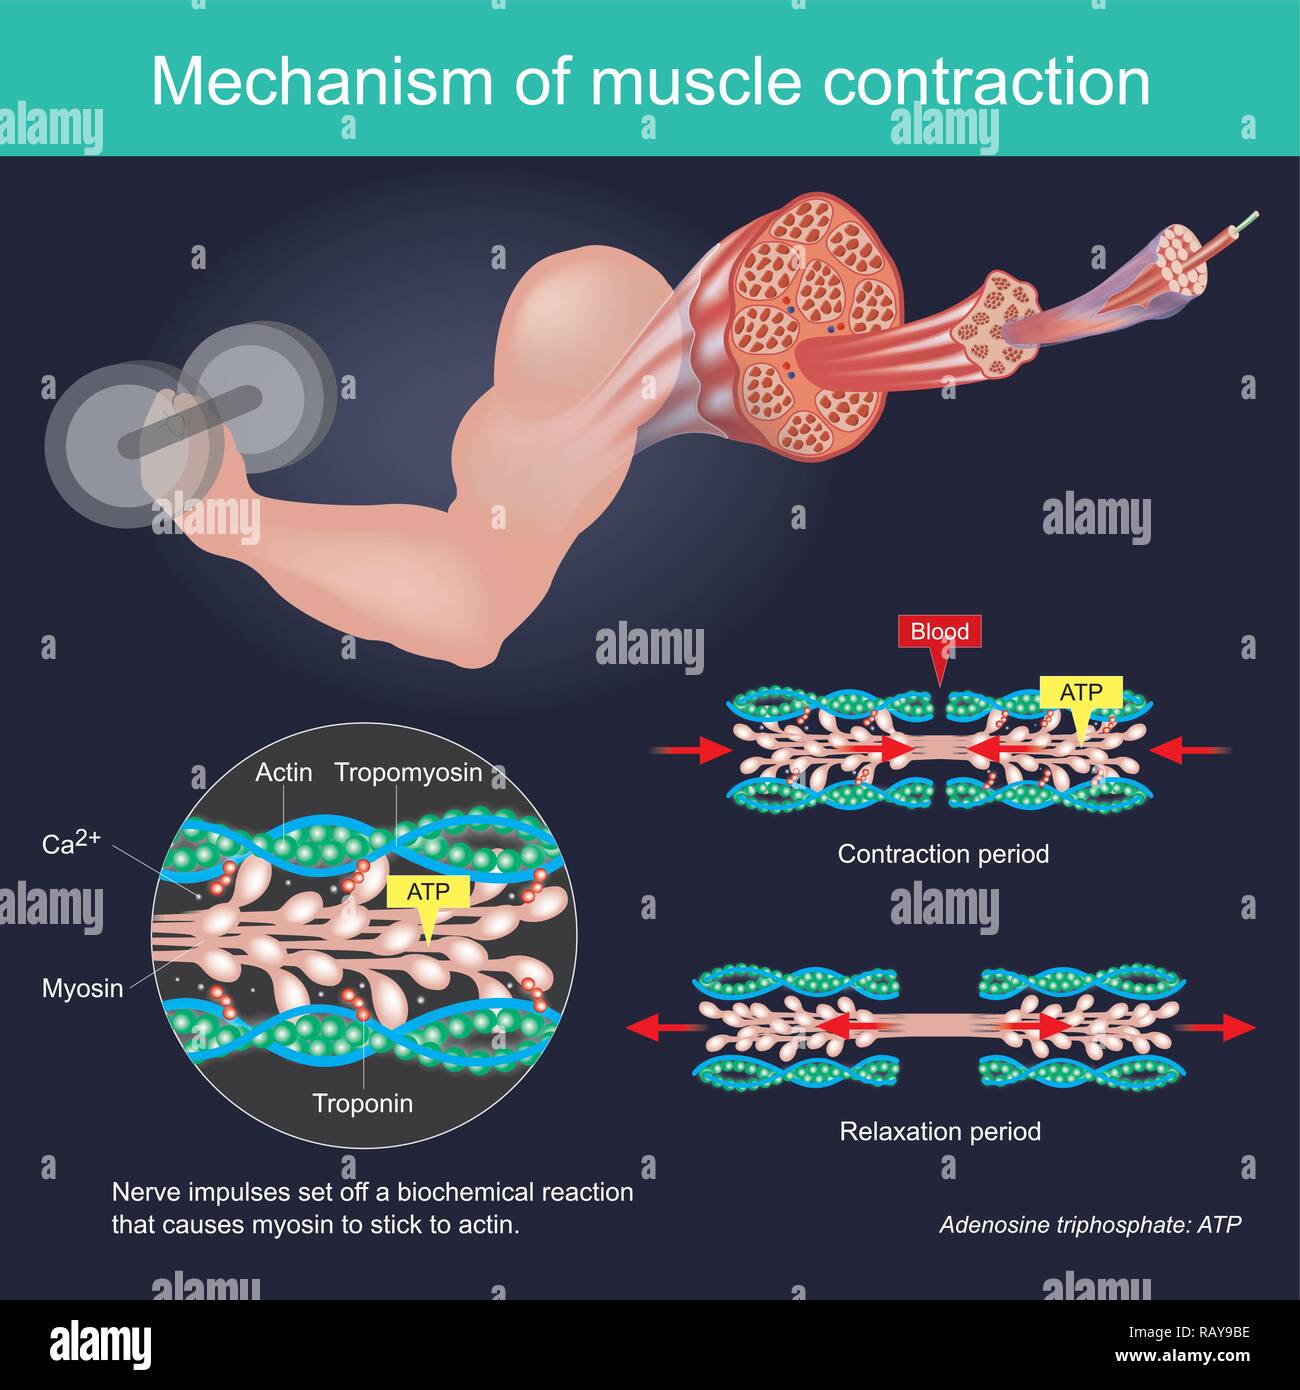

La contrazione muscolare come risultato di impulsi nervosi impostato su off una reazione biochimica che provoca nella miosina di stick di actina. Il corpo umano ed infografico. Illustrazione Vettorialehttps://www.alamy.it/image-license-details/?v=1https://www.alamy.it/la-contrazione-muscolare-come-risultato-di-impulsi-nervosi-impostato-su-off-una-reazione-biochimica-che-provoca-nella-miosina-di-stick-di-actina-il-corpo-umano-ed-infografico-image230481426.html

La contrazione muscolare come risultato di impulsi nervosi impostato su off una reazione biochimica che provoca nella miosina di stick di actina. Il corpo umano ed infografico. Illustrazione Vettorialehttps://www.alamy.it/image-license-details/?v=1https://www.alamy.it/la-contrazione-muscolare-come-risultato-di-impulsi-nervosi-impostato-su-off-una-reazione-biochimica-che-provoca-nella-miosina-di-stick-di-actina-il-corpo-umano-ed-infografico-image230481426.htmlRFRAY9BE–La contrazione muscolare come risultato di impulsi nervosi impostato su off una reazione biochimica che provoca nella miosina di stick di actina. Il corpo umano ed infografico.